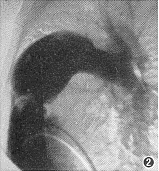

6例X线平片表现为两侧肺血增多,肺门血管扩张,其中有2例肺门呈“残根状”,为右肺动脉受累并重度肺动脉高压。3例表现左侧肺血增多,右侧肺血减少,为左肺动脉受累合并Fallot四联症患者(图1)。5例心脏外形呈二尖瓣型,双侧心室增大,4例呈靴型,右心室增大,主动脉结均有增宽。9例病人心血管造影检查均明确诊断。右心室造影显示主肺动脉显影后仅见1支肺动脉(左或右)显影,患侧肺动脉呈盲端(图2),有6例表现健侧肺动脉明显扩张,主动脉充盈后见另侧肺动脉显影,9例患侧肺动脉均起自升主动脉后壁(图3,4)。

图2 右心室造影(侧位),示右肺动脉异常起源并动脉导管未闭,主肺动脉显影后仅见左侧肺动脉及其分支显影,右肺动脉起始部呈盲端,主肺动脉扩张